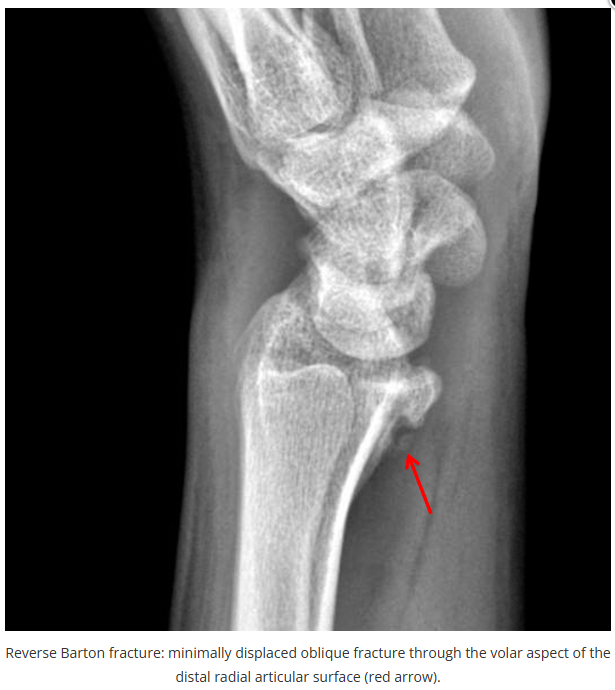

这些腕与手的骨折X线片如果没有标注箭头,你还能识别出来吗?

X线读片是骨科医生的基本功。

今天是腕部与手的X线片。所有X线片都

带有标注和说明

,可以选择长按图片,

自动翻译相关说明

。